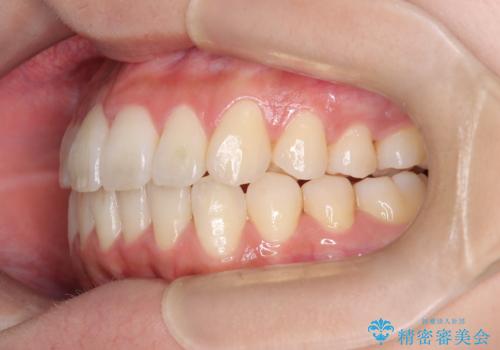

前歯の叢生・Ⅱ級咬合を改善|TADを用いた遠心移動+インビザライン矯正

- 前歯のガタガタと臼歯関係のⅡ級(上顎の歯列が前方にある状態)を改善するため、TAD(歯科矯正用アンカースクリュー)を使用したインビザライン矯正を計画しました。まずTADを上顎の適切な位置に設置し、それを固定源にして奥歯を後方(遠心)へ移動させ、十分なスペースを確保します。その後、インビザラインによるマウスピース矯正で前歯の歯列を整え、臼歯関係を正常化します。治療期間はおよそ1年半〜2年を想定しています。

前歯部の叢生(ガタガタ)と臼歯関係のズレを改善するため、抜歯をせずに奥歯を後方へ移動(遠心移動)させることを選択しました。TADという小型のアンカースクリューを顎骨に設置することで、確実かつ効率的に奥歯を後方へ移動させました。併せて透明で目立ちにくいインビザラインを用いることで、審美性を保ちながら治療を進めることが可能でした。患者様の負担が少ないマウスピース矯正と固定源のTADを組み合わせることで、抜歯することなく歯並びと噛み合わせを大幅に改善でき、大変ご満足いただけました。